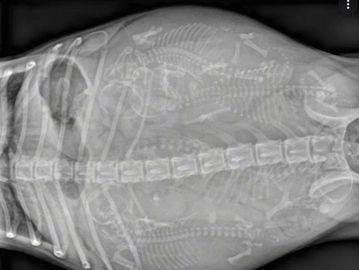

X-rays can distinguish between pregnancy false pregnancy and thickening of the uterus in dogs and are the most accurate estimate of litter size.

. Now that weve established. Counting puppies in an xray can prepare the owner to know how many and if they will fit through the pelvis. X-rays most often give us an exact count of the litter but even with the best images some puppies could be hiding behind another puppy or the dams spine.

I was afraid she would only have one one. Looking again at the X Rays it kinda looks like 7-8 puppies. X-rays most often give us an exact count of the litter but even with the best images some puppies could be hiding behind another puppy or the dams spine.

Joined Jul 5 2020. 15 Marketing Blog Post. The vet confirmed we have 8 on the way and should arrive sometime.

Gypsy had her X-Ray for her puppy count today. X-rays most often give us an exact count of the litter but even with the best images some puppies could be hiding behind another puppy or the dams spine. 3 Jan 20 2022.

While ultrasound is useful for confirmation of pregnancy for dogs and other animals. It takes about 45 days for the puppies bones to mineralize in the uterus meaning they cannot be seen on x-ray before this point. 45 Day Pregnant Dog Xray.

Just try to count their spines. If your dog is about 45 days pregnant he or she might need an xray to check for the pregnancy. Click HERE for more x-ray pictures.

Have you ever seen an X-Ray of a pregnant dog. Ayasha had her pre-partum puppy count x-ray today and the vet confirmed that we are expecting 4 precious puppies.